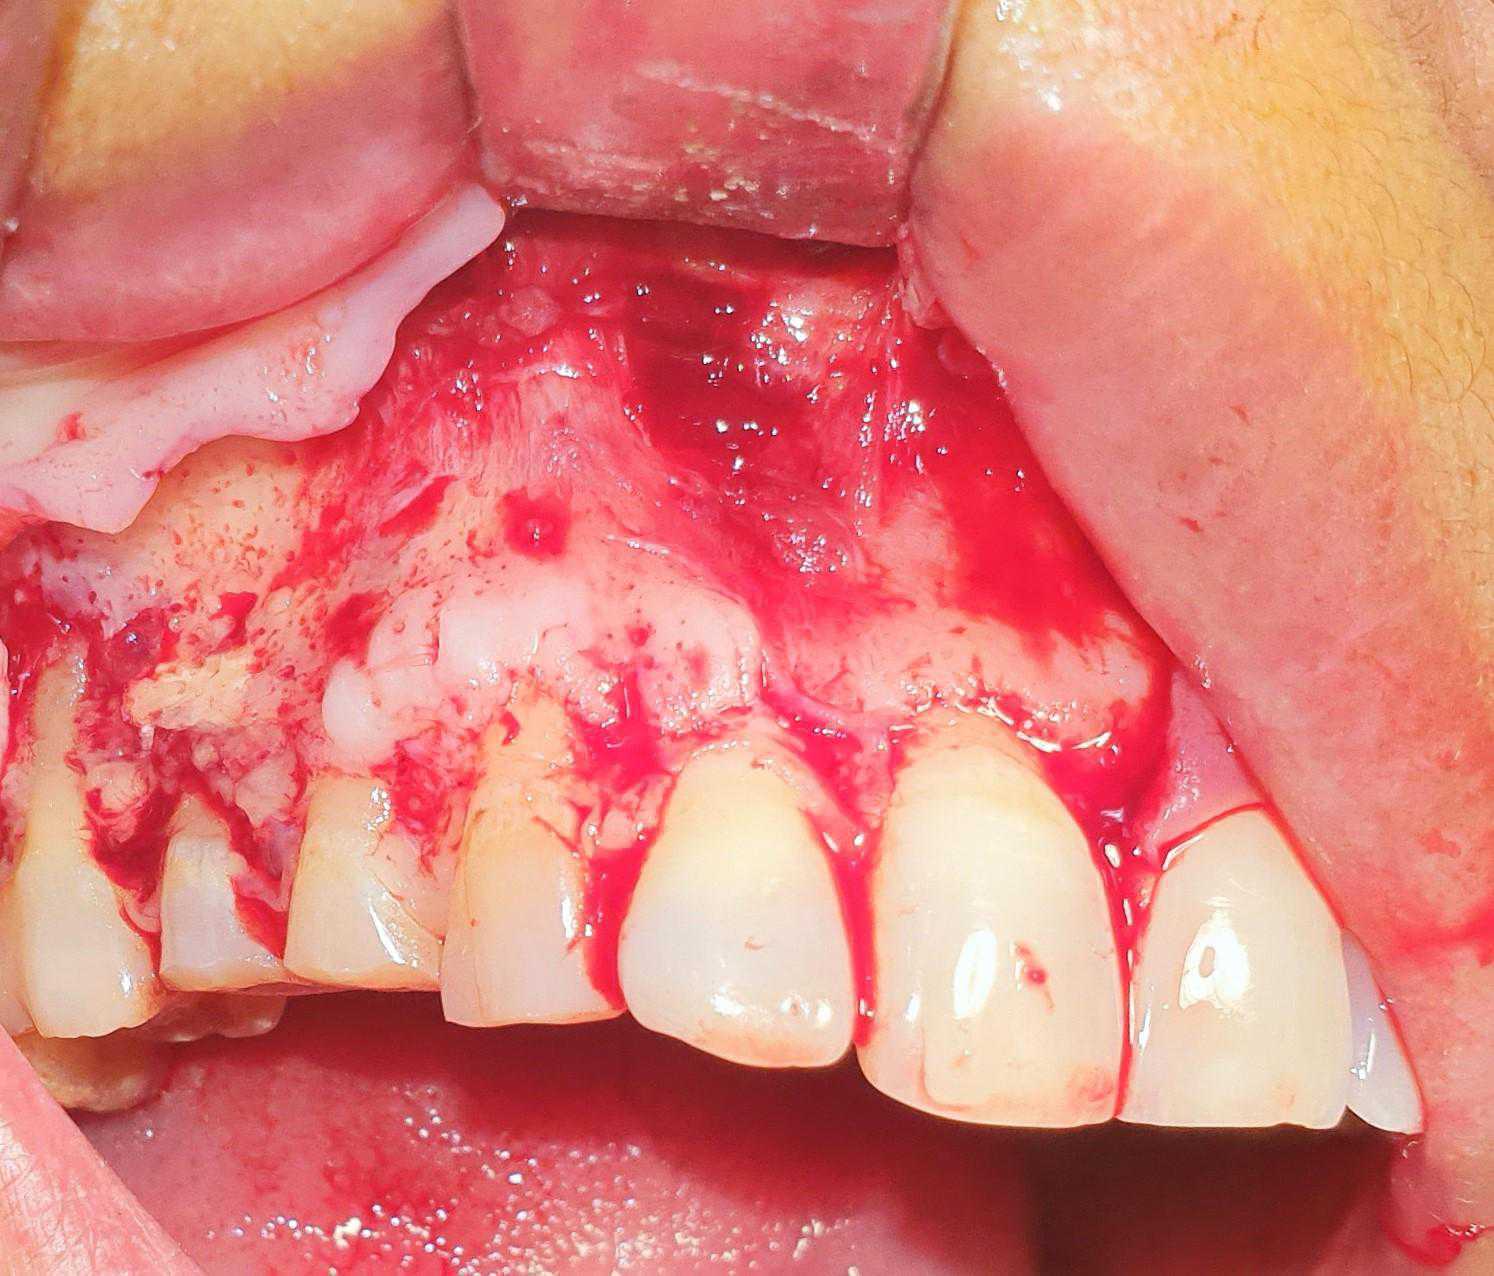

https://demo.discussdentistry.com/forums/topic/post-mucormycosis-avascular-necrosis-of-maxilla-rehabilitation-with-zygomatic/#post-24499 <![CDATA[Post Mucormycosis Avascular necrosis of maxilla, rehabilitation with Zygomatic]]> https://demo.discussdentistry.com/forums/topic/post-mucormycosis-avascular-necrosis-of-maxilla-rehabilitation-with-zygomatic/#post-24499 Thu, 25 Aug 2022 12:14:40 +0000 Sankalp Mittal

• 20210604_101325 (2)20210604_101317 (2)20210604_103315 (2)20210604_102857 (2)20210604_104202 (2)20210604_104853 (2)20210824_105656 (2)20210824_112353 (2)20210824_114957 (2)20210824_131302 (2)20210826_100648 (2)20210826_100749 (2)20210826_100919 (2)20210914_183943 (2)20211001_17535220211012_18543620211012_192043 (2)20211012_185627 (2)20211012_195430 (3)20211027_193725 (2)20211027_200729 (2)20211027_200919